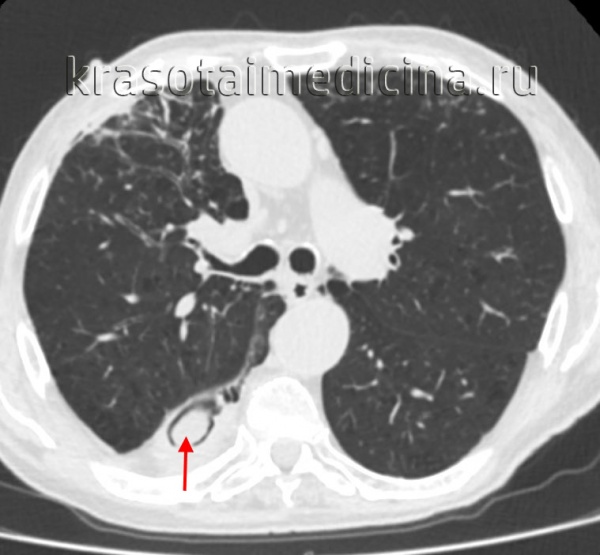

КТ ОГК. Полостное объемное образование в нижней доле правого легкого, частично заполненное грибковыми массами.